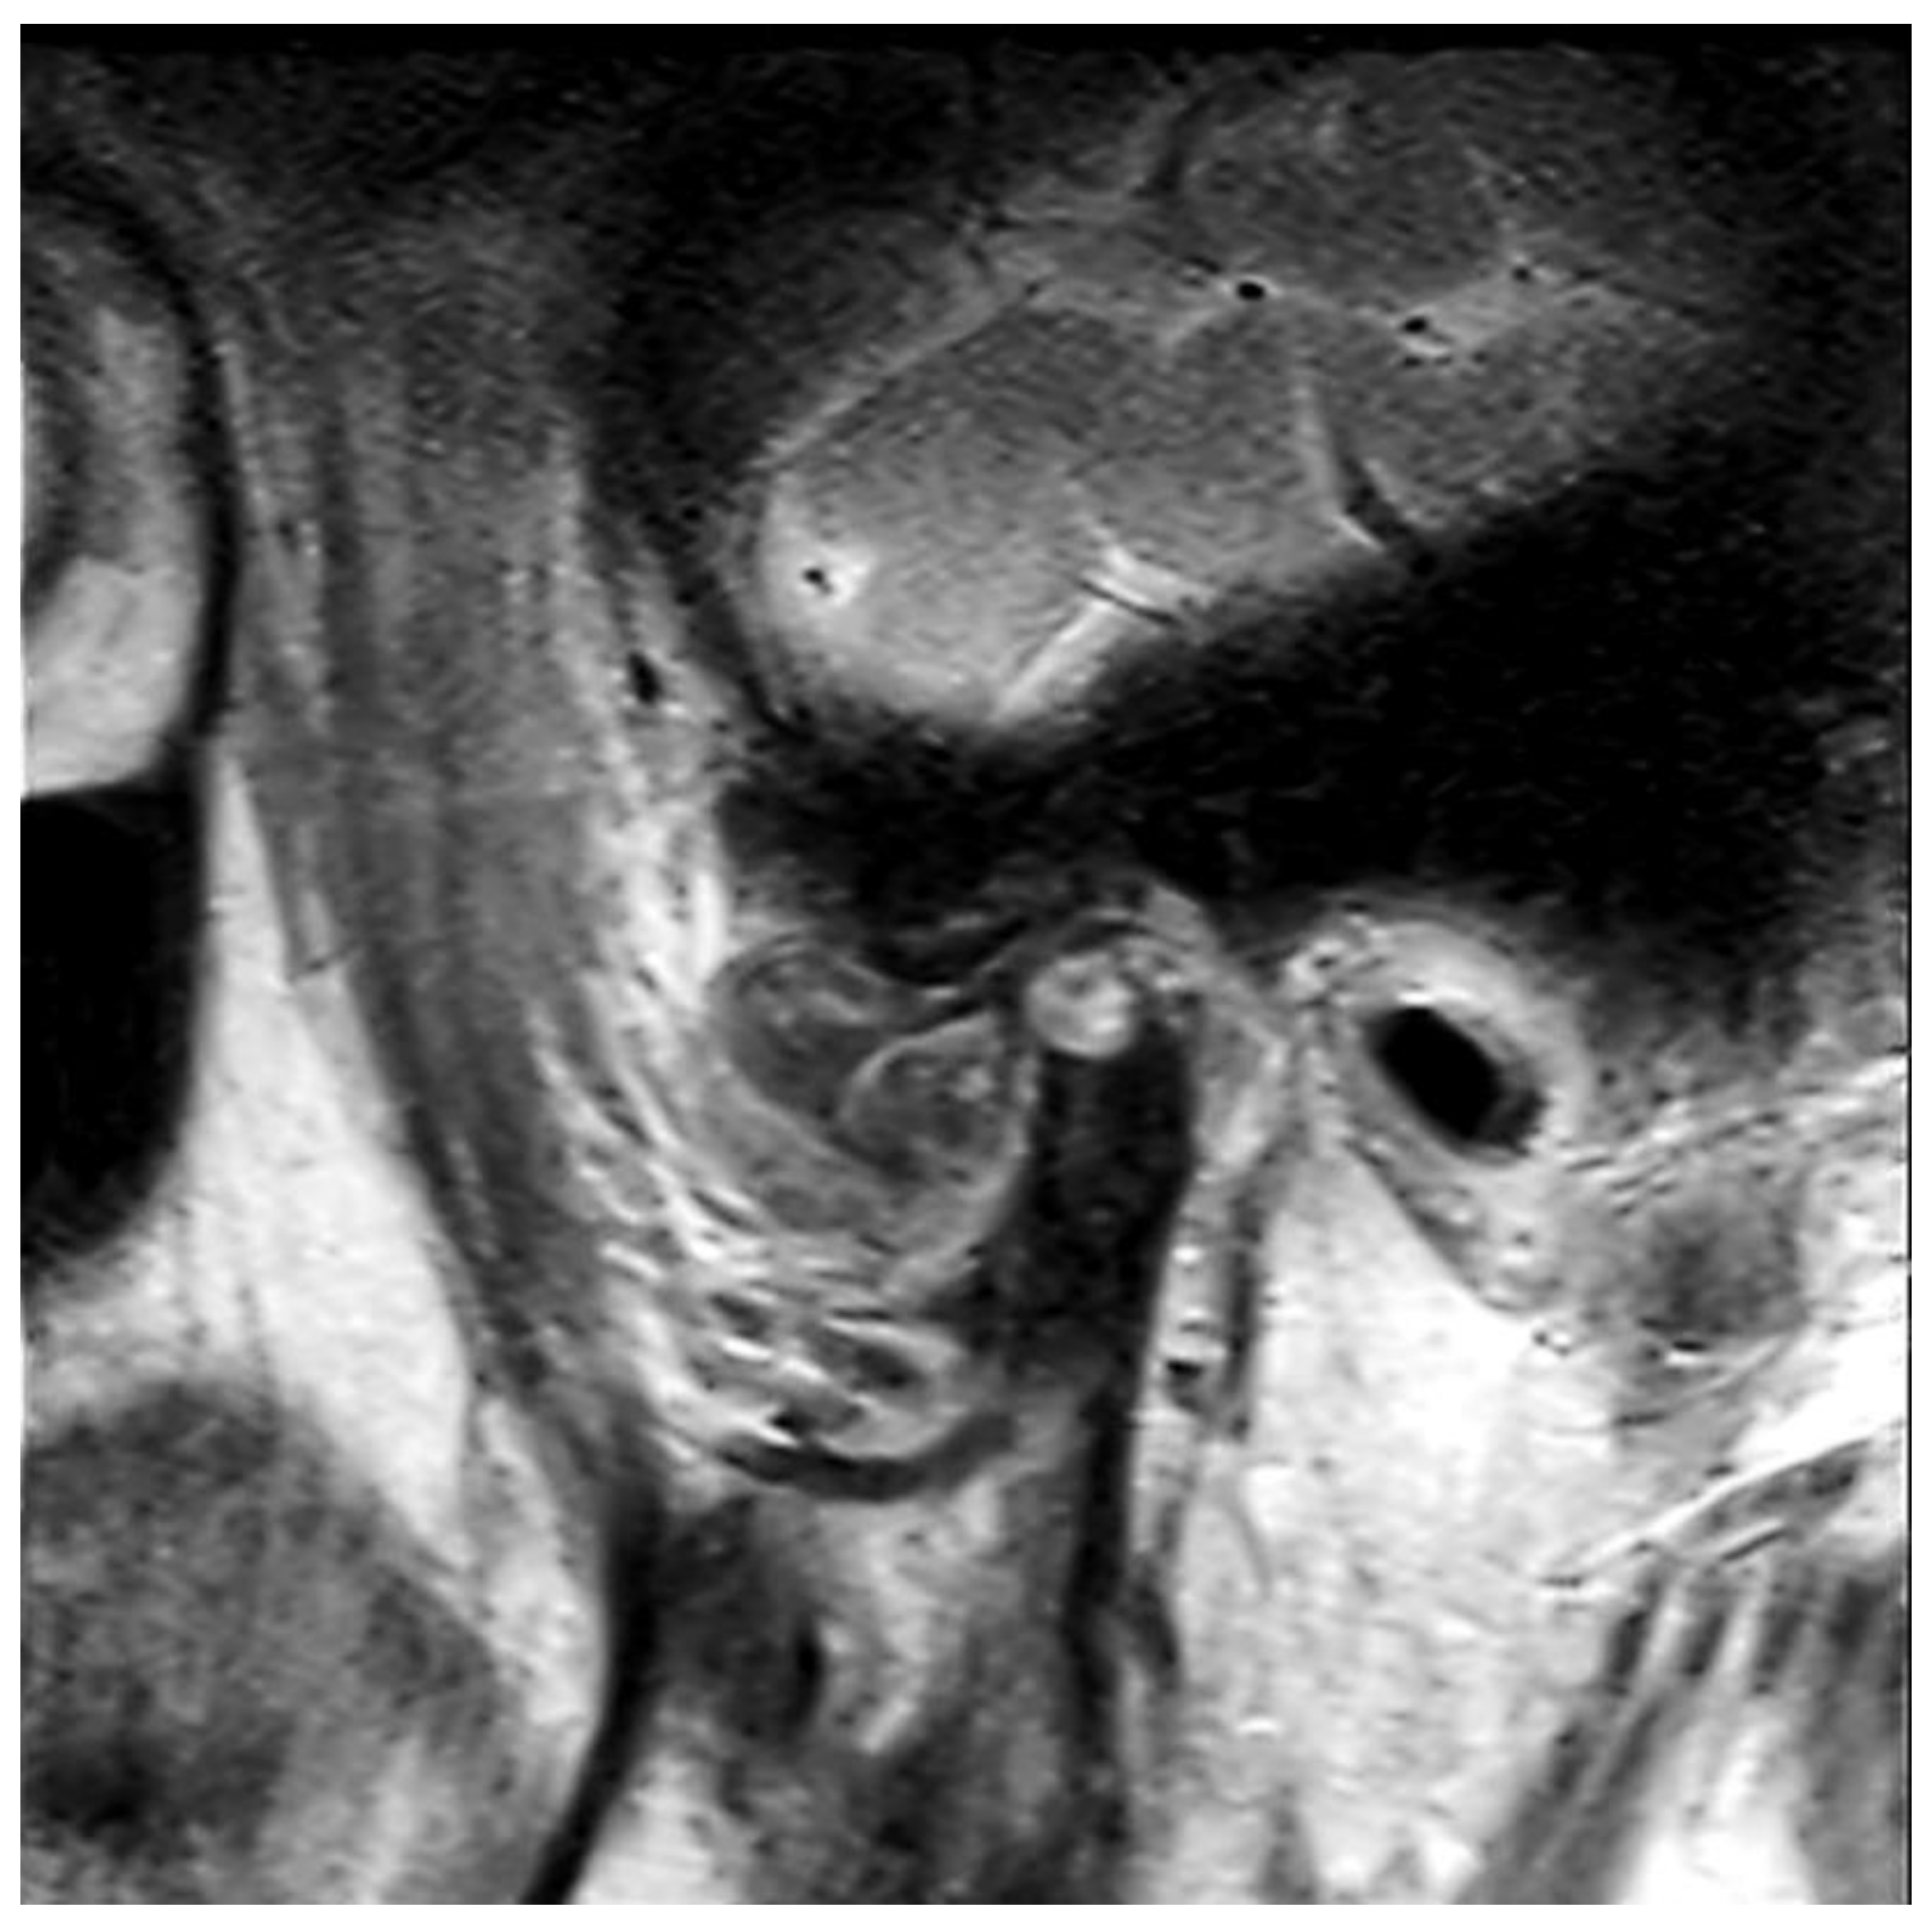

Figure 3.

Magnetic resonance image. Proton density-weighted image of the sagittal plane.

The panoramic radiograph showed an unclear right mandibular condyle with a cloud-like mass (Figure 1). Computed tomography (CT) revealed that the right mandibular condyle was destroyed, and that mottled-like hard tissues had formed around the condyle as viewed on the axial plane (Figure 2A). Similarly, it was confirmed on the coronal plane that the mandibular fossa and cranial base were destroyed. Furthermore, calcified opacity was observed in the bone resorption fossa (Figure 2B). Proton density-weighted imaging showed no disc dislocation in the right TMJ, and the area corresponding to the upper and lower joint space was filled with uneven hypointensity, and the joint space appeared dilated. Additionally, the high signal inside and granular low-signal images were scattered inside the mandibular condyle and fossa (Figure 3). The left TMJ showed no abnormal findings. Based on these findings, we suspected CPPD deposition disease as a clinical diagnosis and excised the lesion under general anesthesia. The right TMJ was exposed using a preauricular approach. During surgery, we confirmed and removed the white chalk-like masses (Figure 4). These masses were present in the articular capsule, articular eminence, mandibular condyle, the upper and lower joint cavities, and articular disc. The maximum size of the masses was 16 × 5 × 5 mm, although various sizes were extracted. CT images were obtained after surgery, and we confirmed that the masses were extracted from the right temporomandibular joint (Figure 5). The postoperative healing was uneventful. This was six months post-surgery, and although the pain in the right TMJ was persistent when opening the mouth, the maximal mouth opening had improved to 42 mm.